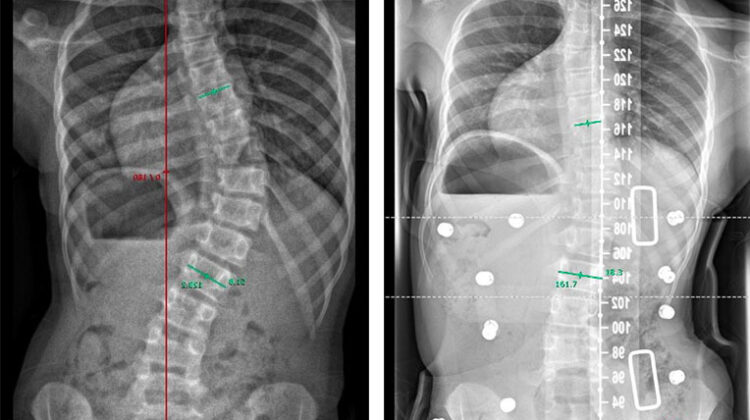

التصحيح داخل الحزام (In-Brace Correction) يعني مقدار تحسن زاوية الانحناء (زاوية كوب – Cobb Angle) عند قياس الأشعة بينما يرتدي المريض الحزام، مقارنة بالقياس قبل بدء العلاج.

تمت دراسة أكثر من 130 مريضًا من المراهقين المصابين باعوجاج العمود الفقري، بزاوية انحناء تتراوح بين 20 و40 درجة، وتم علاجهم بحزام طبي لفترة لا تقل عن عام، حتى اكتمال النمو العظمي.

ثانيًا: أرقام واضحة يجب الانتباه لها

الدراسة حددت قيمًا فاصلة مهمة:

الأطفال والمراهقون الذين لم يكتمل نموهم العظمي

➜ يجب أن تنخفض زاوية الانحناء داخل الحزام إلى أقل من 25 درجةالمراهقون الأقرب لاكتمال النمو

➜ يجب أن تصل زاوية الانحناء داخل الحزام إلى أقل من 30 درجة

الوصول إلى هذه القيم يزيد بشكل كبير من فرصة نجاح العلاج بالحزام.